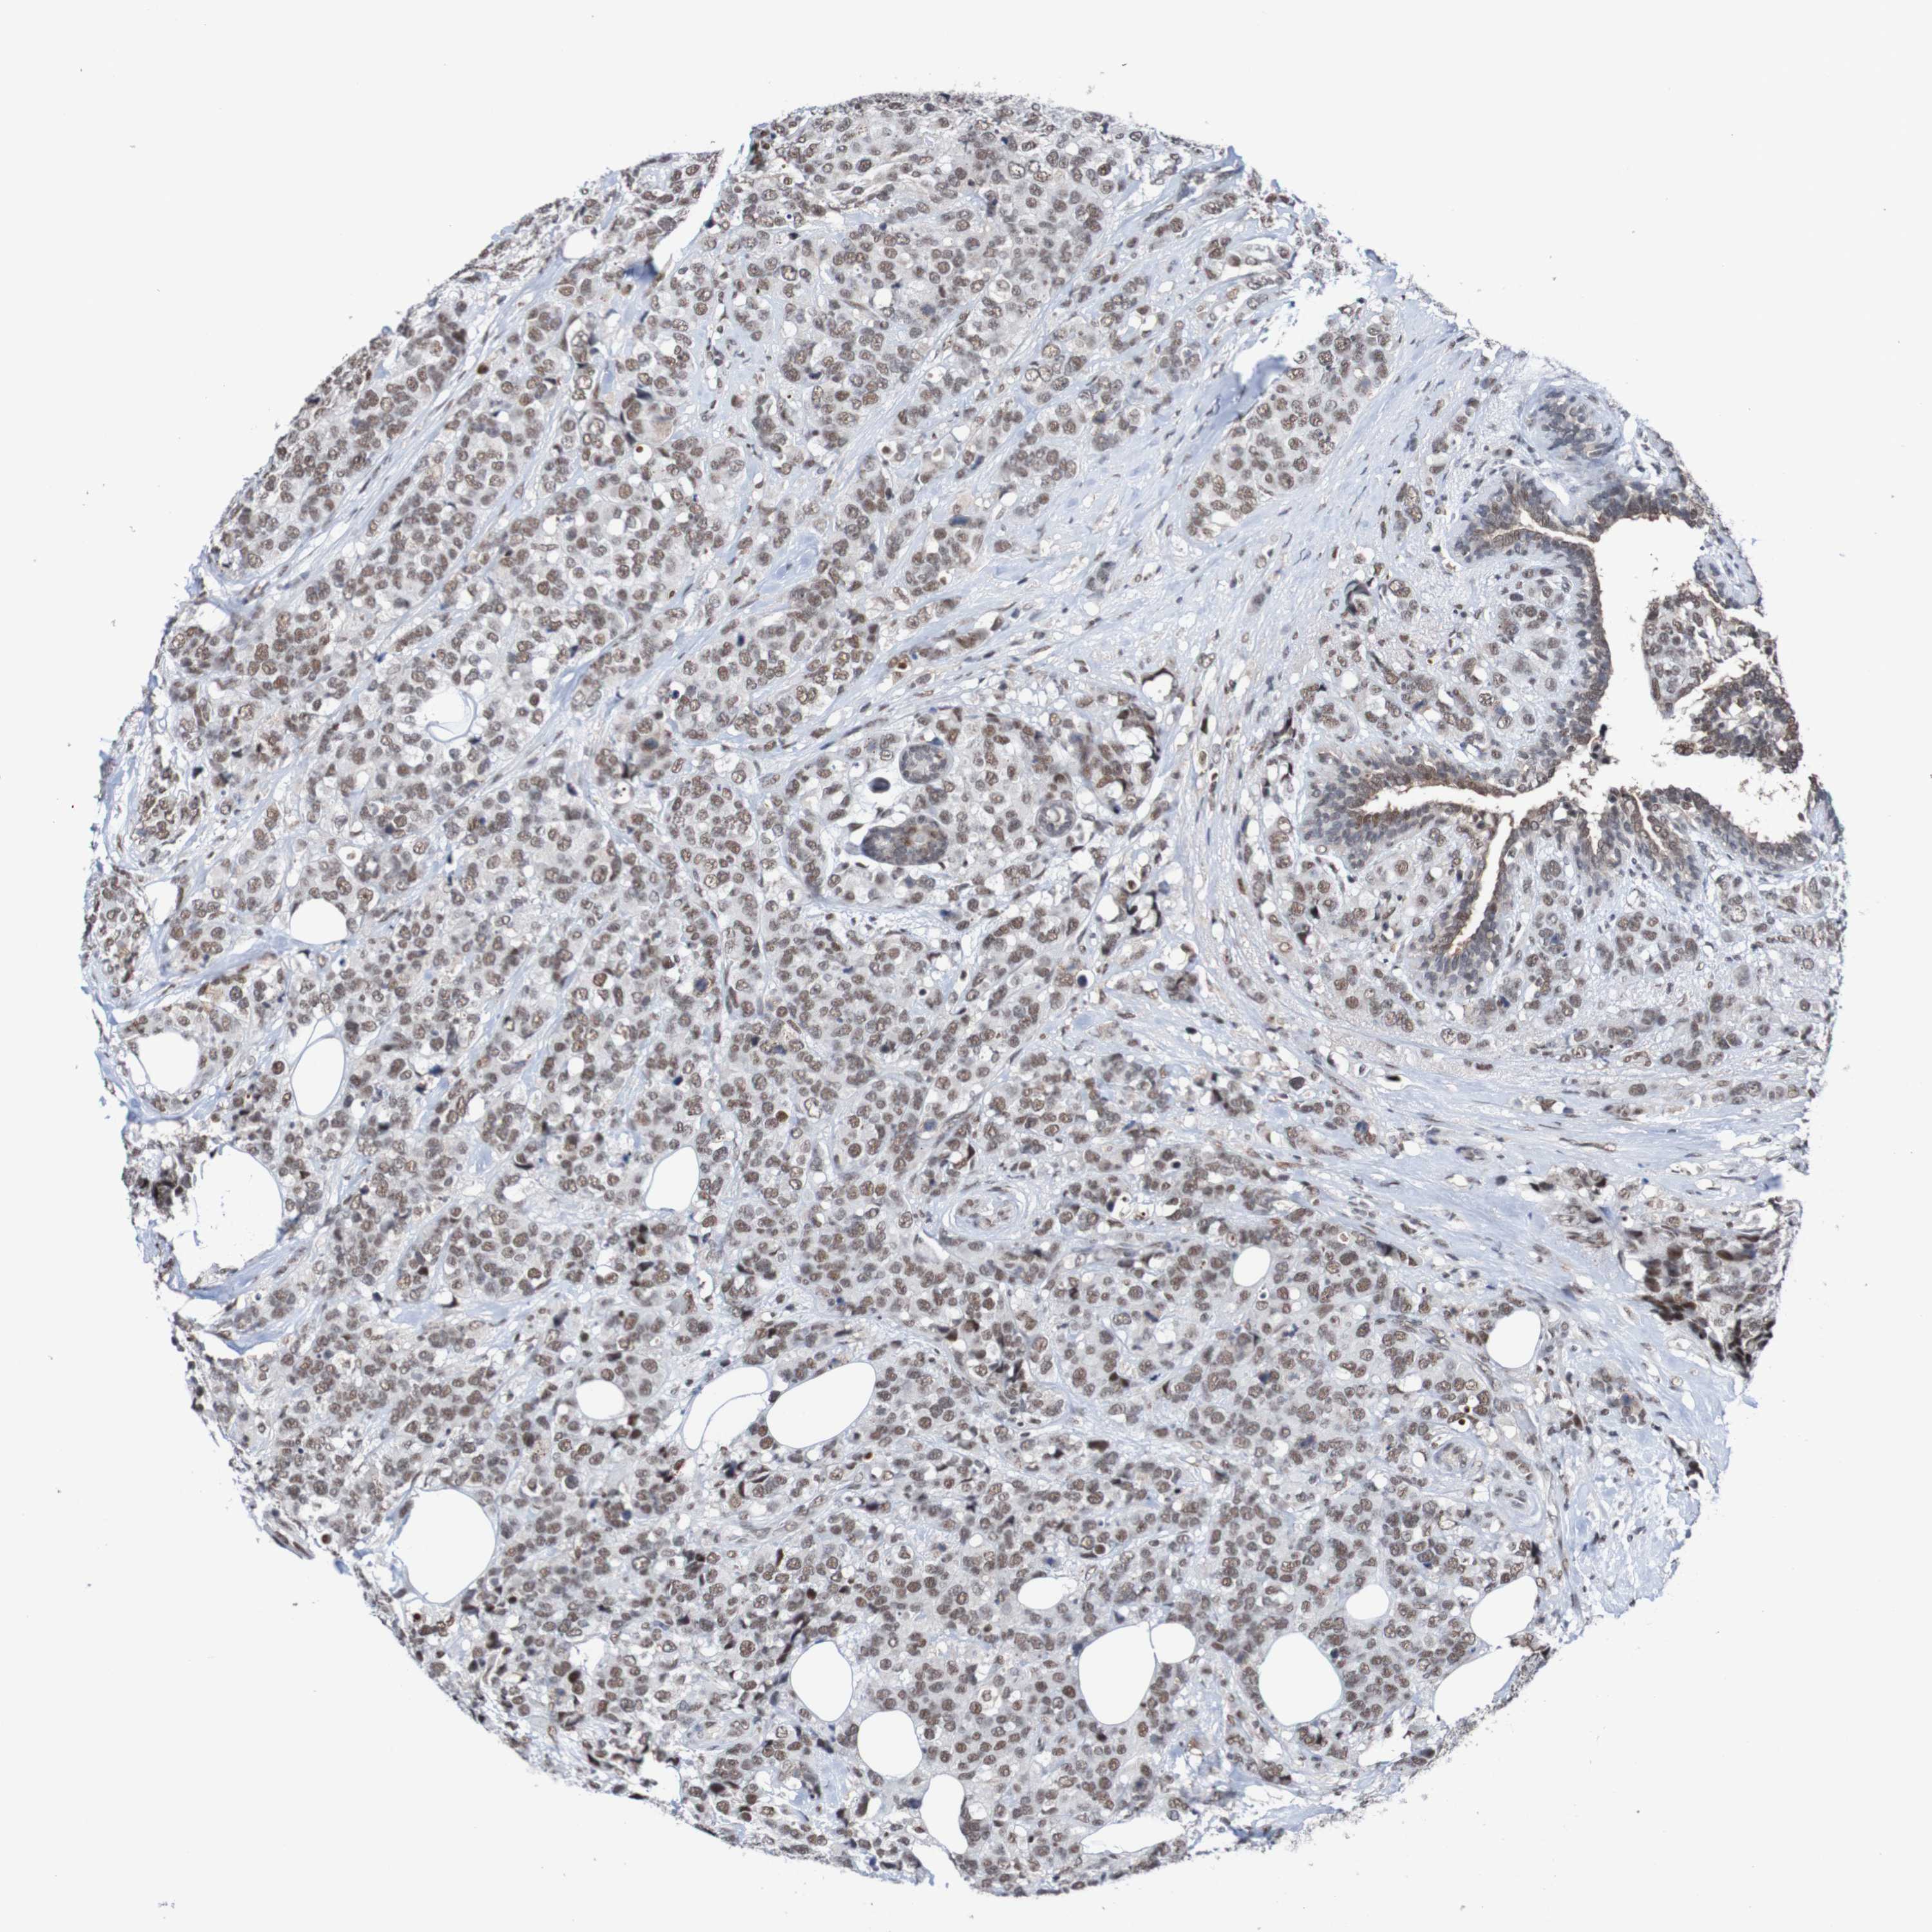

CANCER BREAST CANCER Show tissue menu

BRCA TCGA BRCA VALIDATION PROTEIN EXPRESSION